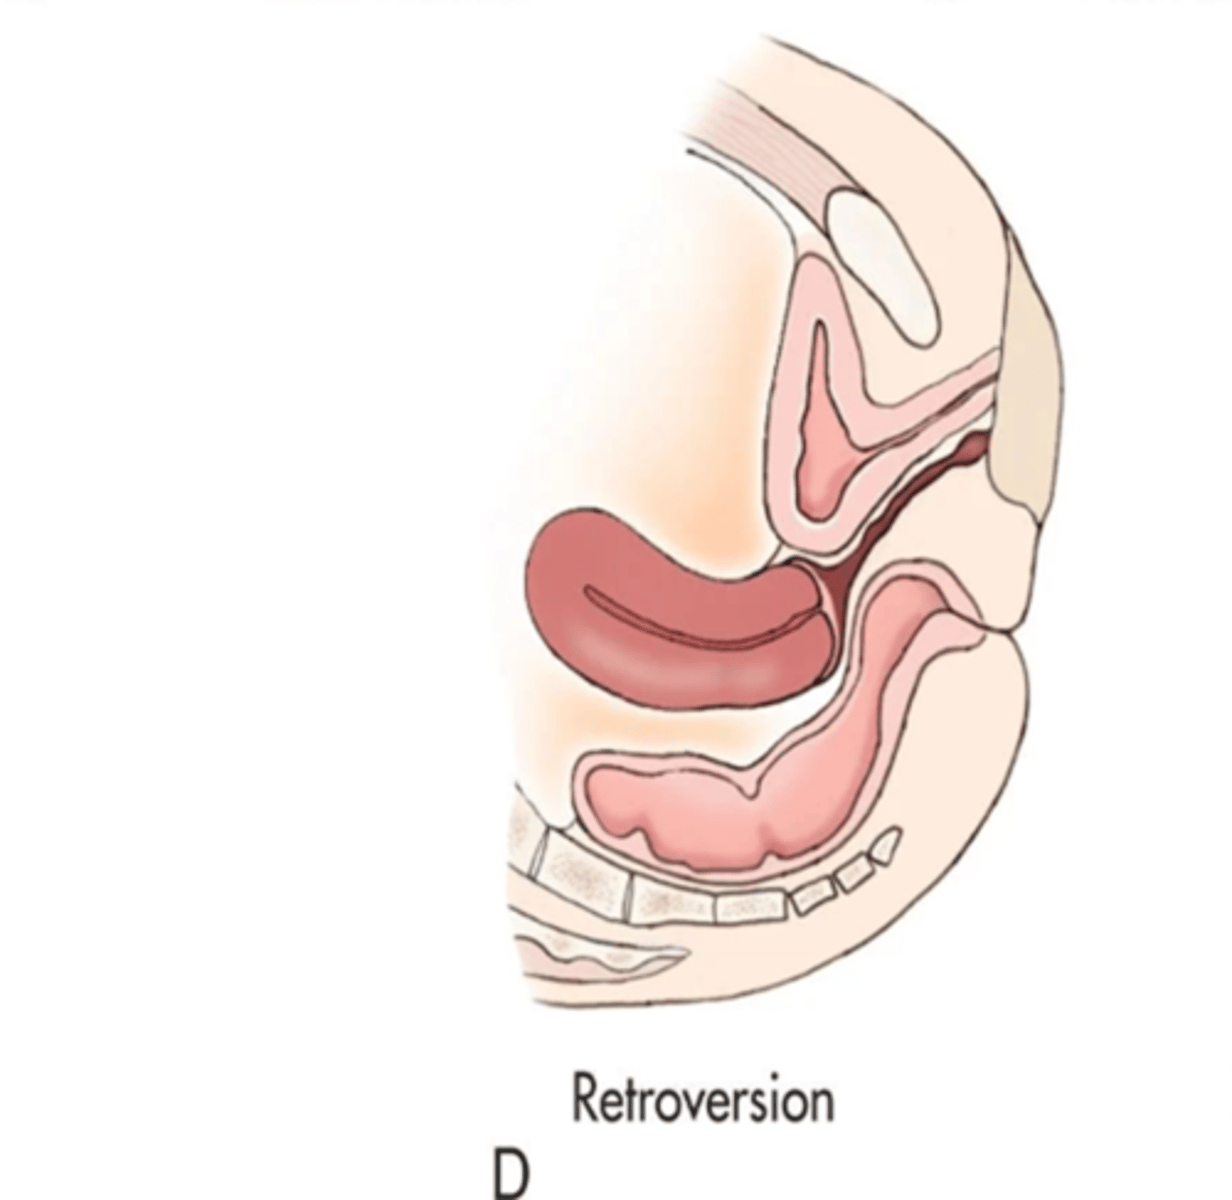

What is a retroverted uterus?

fundus and body tilts backward, fundus and vagina are aligned

A retroverted uterus is common with ___

multiparity

What is a retroflexed uterus?

body and fundus bend backward; fundus is adjacent to cervix and points down